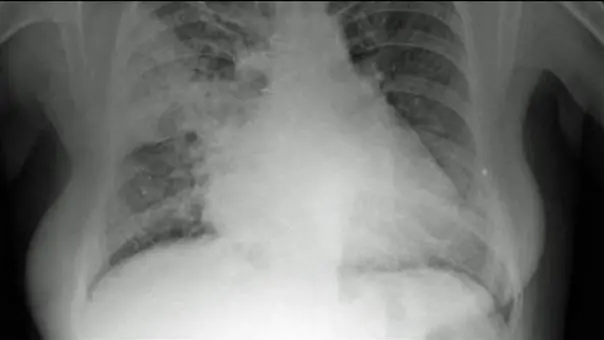

Particelle di grasso killer che, liberate in seguito alla distruzione delle cellule adipose, viaggiano nel sangue raggiungendo più organi e che, una volta arrivate nei polmoni, si appiattiscono sugli alveoli formando una membrava che li avvolge e toglie il respiro: è il meccanismo all’origine delle polmoniti bilaterali da Covid-19, ricostruito per la prima volta dal gruppo di ricerca italiano pubblicato sull’International Journal of Obesity. Ci sono voluti quasi due anni di lavoro per ricostruirlo, ma alla fine il quadro è completo, grazie alla ricerca coordinata da Saverio Cinti, dell’Università Politecnica delle Marche, e condotta in collaborazione con l’Università di Milano e con l’Université Còte d’Azur.

I nuovi dati, raccolti dai tessuti di 19 individui deceduti per Covid-19 e di 23 morti per altre cause, confermano l’ipotesi pubblicata nel 2020 dallo stesso gruppo di ricerca, ossia che la malattia causata dal virus SarsCoV2 «determina embolie grassose responsabili delle polmoniti bilaterali», ha detto Cinti all’ANSA. «Le implicazioni per la terapia sono importanti – ha aggiunto – perché, secondo me e i farmacologi che hanno partecipato alla ricerca, sarebbe bene intervenire il più precocemente possibile con farmaci antinfiammatori liposolubili». Farmaci di questo tipo, in grado di sciogliersi nei grassi, permetterebbero di aggredire i lipidi liberati nel sangue dopo la distruzione delle cellule adipose. Quest’ultimo fenomeno avviene perchè nelle persone obese le cellule adipose sono costantemente sottoposte alla richiesta di immagazzinare più grassi e progressivamente si ingrandiscono e accumulano stress, fino a disgregarsi e a morire.